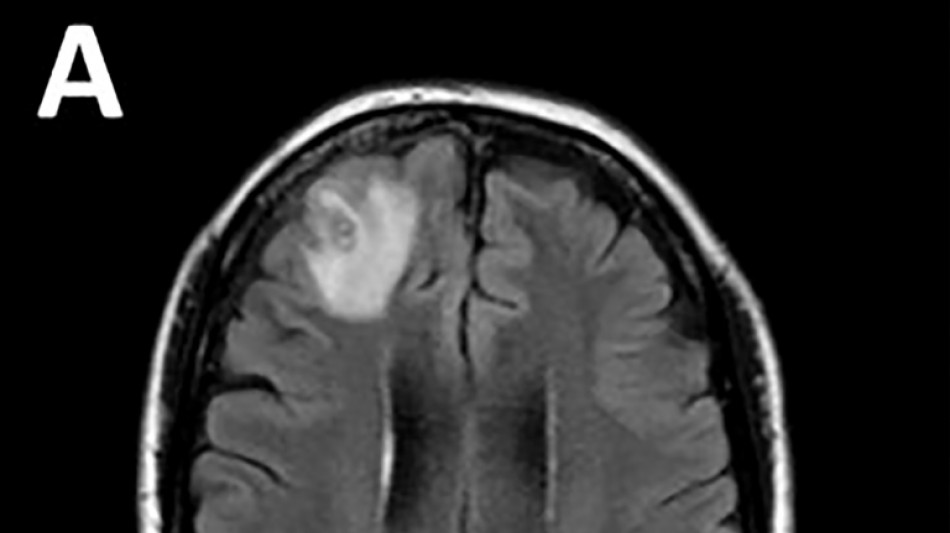

Médicos australianos hallan por primera vez una lombriz parásita en el cerebro de una mujer / Foto: Handout - Universidad Nacional Australiana/AFP

Desconcertados, los médicos realizaron una resonancia magnética a una mujer australiana de 64 años después de que comenzara a sufrir lapsos de memoria y notaron una "lesión atípica" en el frente de su cerebro.

Era una lombriz de ocho centímetros llamada Ophidascaris robertsi, que según investigadores son parásitos comunes en canguros y pitones diamantina pero no en humanos.